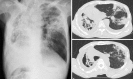

A 75-year-old man was diagnosed with pulmonary nontuberculous mycobacterial (NTM) infection in February 2005 and was treated with rifampicin, ethambutol, and clarithromycin. However, the infection was resistant to treatment, and his chest radiograph showed an abnormality that gradually seemed to aggravate. The patient's sputum was positive for Mycobacteria. Moreover, the patient had dyspnea and an underlying chronic inflammation in the lungs. He visited our hospital because of dyspnea and leg edema in June 2011. Laboratory evaluation on admission revealed proteinuria (6 g/day) and decreased serum total protein (5.8 g/dL) and albumin (1.6 g/dL) levels, indicating nephrotic syndrome. Percutaneous renal biopsy revealed membranoproliferative glomerulonephritis (MPGN) in the acute stage and AA amyloidosis of mild degree. AA amyloidosis was also diagnosed histologically on gastric and colonic biopsy, in addition to renal biopsy. His renal function decreased gradually, and therefore, he underwent hemodialysis therapy in January 2012. However, his gastrointestinal-related symptoms persisted, and his appetite diminished, because of which he had become severely malnourished; he died 8 months later. This is a rare case of a patient with two different renal lesions (MPGN and AA amyloidosis) complicated with NTM. Our case suggests that MPGN and amyloidosis should be considered in elderly patients with nephrotic syndrome onset and chronic inflammation.